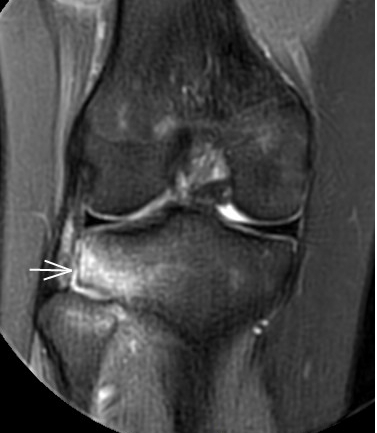

2. 運動后“打軟腿”——韌帶的“斷弦危機”

場景:打球急停后膝蓋不穩(wěn),走路像“踩棉花”

MRI偵查:揪出前交叉韌帶斷裂(呈“波浪狀”或連續(xù)性中斷)、內(nèi)側(cè)副韌帶損傷,防止關(guān)節(jié)“脫軌”

(內(nèi)側(cè)副韌帶損傷)